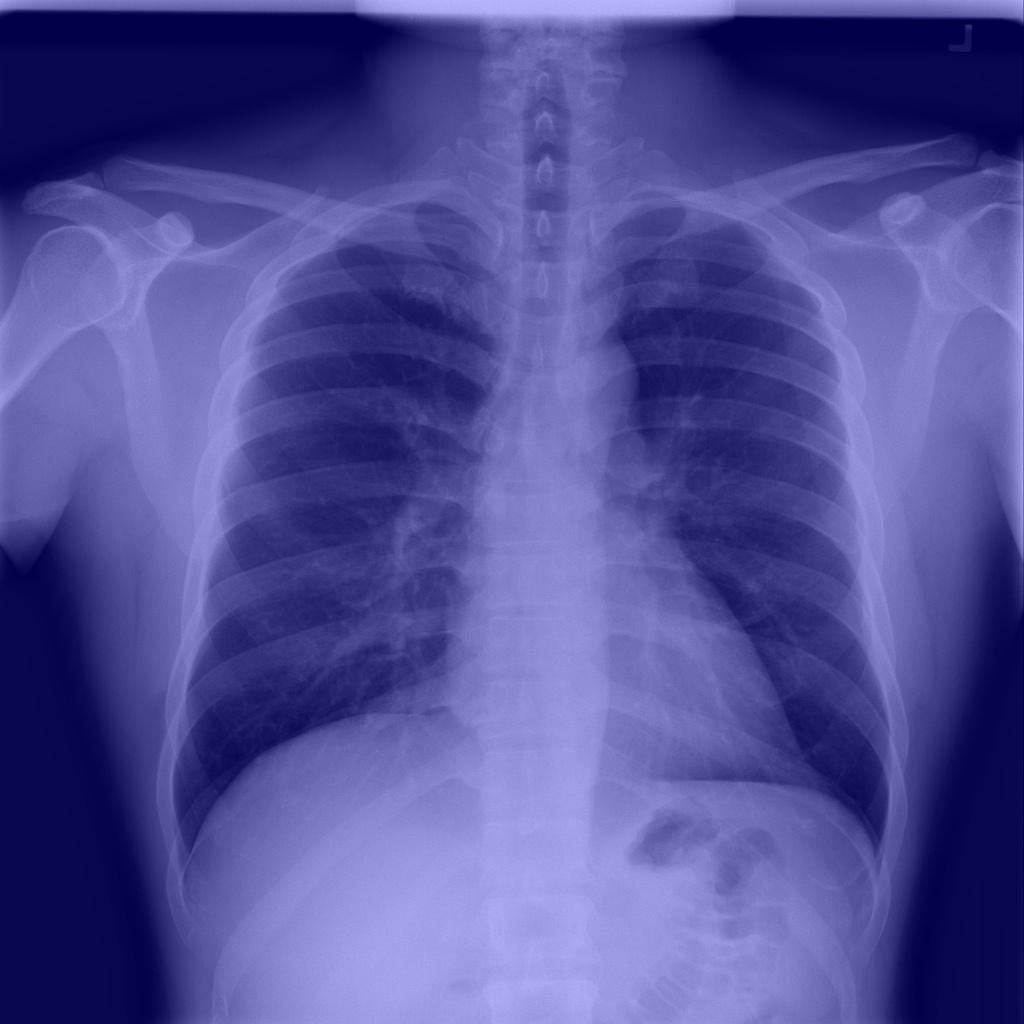

In this sub-section, we concisely inaugurate the benchmark data set, named COVIDx[22], that used in our experiment. To the best of our knowledge, this data set is one of the largest open-access benchmark data set for the number of COVID-19 infection cases, and the total number of 14,914 images for training and 1,579 images for testing, comprising three categories of COVID-19, normal and pneumonia333Access on July 17, 2020. Figure 1 shows sample images from the benchmark dataset, including COVID-19, normal and pneumonia. Table 2 depicts the distribution of images in training and testing sets. To generate the COVIDx, the authors[22] used five different publicly accessible data repositories:

Refer to caption

(a) COVID-19

(b) Normal

(c) Pneumonia

Figure 1: Some image labels available in the benchmark dataset [22]